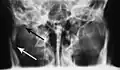

Towne's view of a bilateral condyle fracture. White arrow is a fracture on the neck of the condyle. Black arrow shows the condyle pulled to the medial. The same injury can be seen on the opposite side